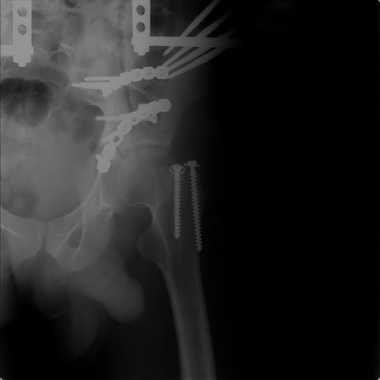

Добрый вечер, уважаемые коллеги. Прошу прощение за долгое молчание( компьютер был в долгосрочном ремонте). Больного с 9-ти месячной травмой таза мы прооперировали. Оценив свои возможности и совместив с вашими рекомендациями и советами (большое спасибо Рункову!), пошли задне-наружным доступом, с отсечением большого вертела. Закрепились 2-мя пластинками. Сверху закрепили аппаратом( передней рамой). На область перелома самого гребня повздошной кости не вмешивались. Снимки высылаю. Жду ваших отзывов и комментариев. Всем большое спасибо за активное участие в лечении больного. С ув.Андрей

Внутренняя фиксация получилась достаточно стабильная.А передняя рама наложена с целью дополнительной фиксации для нейтрализации мышц прикрепляющихся к крылу подвздошной кости, и исключить возможное расшатывание и возникнование нестабильности внутрених фиксаторов( уж очень большая нагрузка на эти 2 пластины).На открытом этапе операции мобилизовали только часть линии всего перелома( около 1/4 части начиная от свода и проксимально), а остальная часть находится в рубце и патологическая подвижность в ней есть хоть и не выражена) А о ранней нагрузке никто и не думал. А как на ваш взгляд, в какие сроки в такой ситуации разрешить полную нагрузку? Я считаю, что только при сращении перелома, подвержденные лучше бы КТ